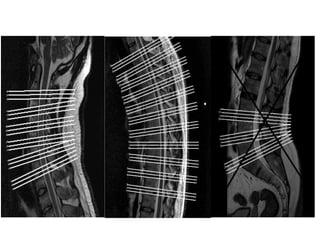

ESPONDILOLISTESE